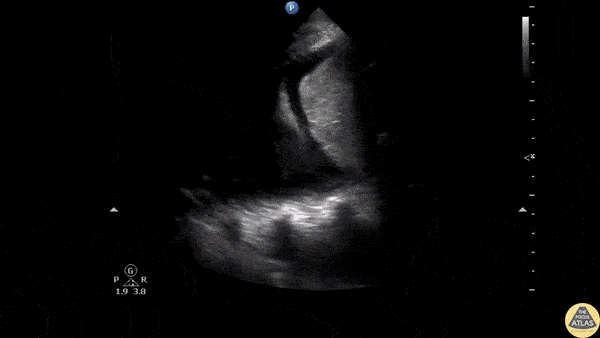

A male presented to the ED following a gunshot wound to the left chest. The perisplenic window of the FAST exam revealed a left hemothorax with a large subpleural area of clotted blood. Image courtesy of Robert Jones DO, FACEP @RJonesSonoEM Director, Emergency Ultrasound; MetroHealth Medical Center; Professor, Case Western Reserve Medical School, Cleveland, OH View his original post here